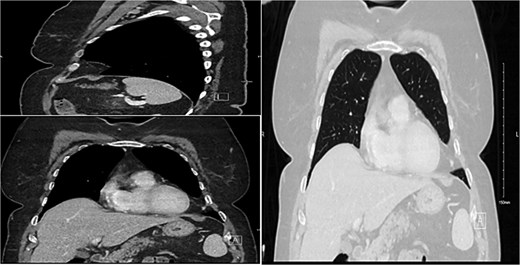

Case presentation

This is a 56-year-old female referred to our clinic with on-and-off left pleuritic chest pain since 3 months. Her past medical history was significant for hypothyroidism and dyslipidaemia. Upon presentation, she was conscious, alert, oriented, with normal vital signs, not in respiratory distress. Her laboratory workup unremarkable, chest X-ray was unremarkable for any abnormality, and computed tomography scan of the chest with IV contrast (Fig. 1) showed features suggestive of benign left pleural lipoma with no effusion or pleural thickening. Preoperative tests were done, the patient underwent surgical resection via VATS by a 10-year expert consultant. The operation was done uneventfully and specimen was sent to laboratory that revealed the diagnosis of pleural lipoma (Fig. 2). Patient postoperative period was uneventful, discharged after surgery and followed up in clinic for 1 month with resolving of her symptoms completely and return to her normal life activities safely.

Demonstration of a pleural-based soft tissue mass consistent with lipoma.

Pleural lipomas do not have a risk of malignant transformation and are typically asymptomatic [10]. However, we believe our patient presenting symptom pleuritic chest pain is due to the lipoma, as the patient intra-operatively was found to have this lipoma attached to intercostal space and adhered to the lung and pericardial fat. As a result of this attachment to the intercostal space a traction effect on the nerve might contribute to her presentation. Diagnostically, CT imaging has superiority over X-ray and ultrasound due to its accuracy in thoracic lipomas [10]. Additionally, it has a characteristic of homogeneity, obtuse-angled, fat-attenuating mass allows a definitive diagnosis of lipoma on CT [11]. However, there are case reports of lipomas containing fibrous stroma or dystrophic ring-type calcifications that make diagnosis sometimes challenging based on radiological evidence alone [12, 13]. As a result, a histopathological investigation is recommended to differentiate between similarly presenting fat-containing intrathoracic masses such as our case.